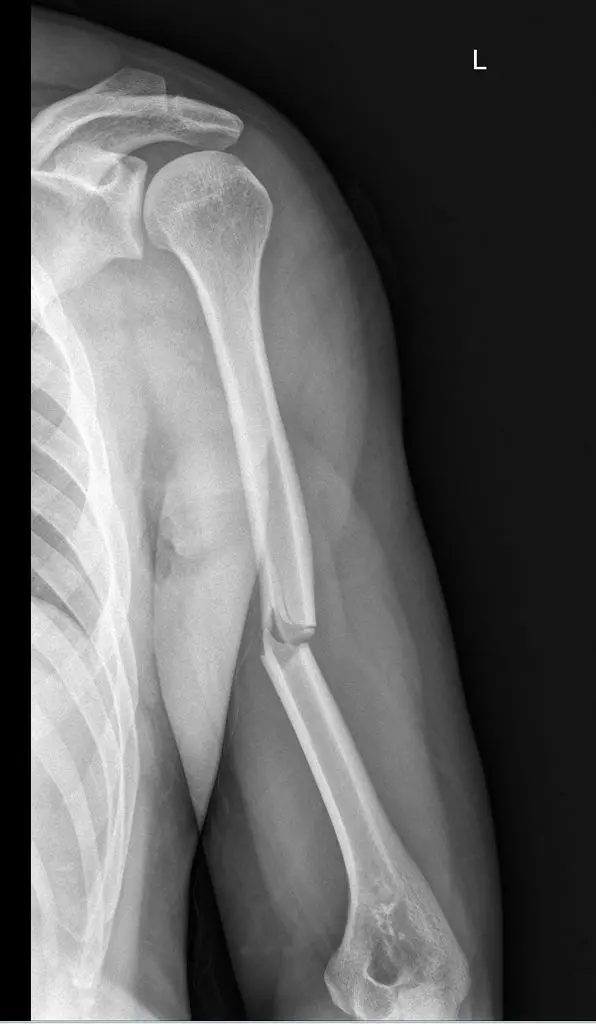

1. Can you describe this radiograph?

The image shows dorsal dislocation of the capitate which should be congruous with the cup of the lunate.

## Perilunate Dislocations and Fracture-Dislocations The lunate, which is normally securely attached to the distal radius by ligamentous attachments, is commonly referred to as the โcarpal keystone.โ ## Greater Arc Injury Greater arc injury passes through the scaphoid, capitate, triquetrum, or distal radial styloid and often results in transscaphoid, transcapitate, or transradial styloid perilunate fracture-dislocations.  ## Lesser Arc Injury Lesser arc injury follows a curved path around the lunate, involving only the capsuloligamentous tissues through the scapholunate ligament, midcarpal joint, and lunotriquetral ligaments and results in perilunate and lunate dislocations. The most common injury is transscaphoid perilunate fracture-dislocation. Disruption of the normal kinematics and stability of the carpal row lead to acute failure with a predictable pattern of posttraumatic changes.  ## Mechanism of Injury Perilunate injuries: Axial load is applied to the thenar eminence, forcing the wrist into extension. Injury progresses through several stages (Mayfield progression): It usually begins radially through the body of scaphoid (fracture) or through scapholunate interval (dissociation), although both are possible in the same injury (rare). Force is then transmitted ulnarly through the space of Poirier (between the lunate and capitate). Subsequently, force transmission disrupts the lunotriquetral articulation. This results in dorsal dislocation of the capitate and rest of the carpus relative to the lunate. Finally, the lunate can dislocate volarly out of the lunate fossa of the distal radius, in which case it is called the lunate dislocation. In a lunate dislocation, the proximal part of the capitate sits in the lunate fossa. ## Clinical Evaluation Scapholunate or perilunate injuries typically cause tenderness just distal to Lister tubercle. Swelling is generalized about the wrist with variable dorsal prominence of the entire carpus in cases of dorsal perilunate dislocations. ## Radiographic Evaluation PA, lateral, and oblique views should be obtained to confirm the diagnosis and rule out associated injuries. A CT scan may be useful in further defining the injury pattern. * **PA View** The dislocated lunate appears to be wedge-shaped and more triangular, with an elongated volar lip. Loss of normal carpal colinear โGilula linesโ and abnormal widening of the scapholunate interval >3 mm are noted. Look for associated fractures, such as โtransscaphoidโ injuries.  * **Lateral View** Most important view. Carefully look at the outline of the capitate and lunate. The โspilled teacup signโ occurs with volar dislocation of the lunate. A clenched-fist PA view obtained after closed reduction of the midcarpal joint is useful for checking residual scapholunate or lunotriquetral dissociation as well as fractures.  ## Classification (Mayfield) | Stage | Description | | :------ | :----------------------------------------------------------------------------------------------------------------------------------------------------------------------------------------------------------------------- | | Stage I | Disruption of the scapholunate joint: The radioscapholunate and interosseous scapholunate ligaments are disrupted. | | Stage II | Disruption of the midcarpal (capitolunate) joint: The radioscaphocapitate ligament is disrupted. | | Stage III | Disruption of the lunotriquetral joint: The distal limb of the radiolunotriquetral ligament and the ulnotriquetrocapitate complex is disrupted. | | Stage IV | Disruption of the radiolunate joint: The dorsal radiolunotriquetral ligament is disrupted, ultimately causing volar dislocation of the lunate. | ## Treatment Closed reduction should be performed with adequate sedation. Closed reduction of lunate dislocations is frequently unsuccessful. Early surgical reconstruction is performed if swelling allows. Immediate surgery including open carpal tunnel release is needed if there are progressive signs of median nerve compromise. Most transscaphoid perilunate dislocations are best treated by open volar and dorsal reduction and repair of the injured structures. Open repair should be supplemented by pin fixation while ligaments heal. Delayed reconstruction is indicated if early intervention is not feasible. ## Complications * Median neuropathy may result from carpal tunnel compression, necessitating surgical release. * Posttraumatic arthritis may result from the initial injury or secondarily from small, retained osseous fragments and cartilage damage. * Chronic perilunate injury may result from untreated or inadequately treated dislocation or fracture-dislocation resulting in chronic pain, instability, and wrist deformity, often associated with tendon rupture or increasing nerve symptoms. * Recurrent instability may necessitate ligament reconstruction with capsular augmentation. * If recurrent instability persists, lunotriquetral fusion may be necessary, with possible concomitant ulnar shortening to tension the volar ulnocarpal ligaments.